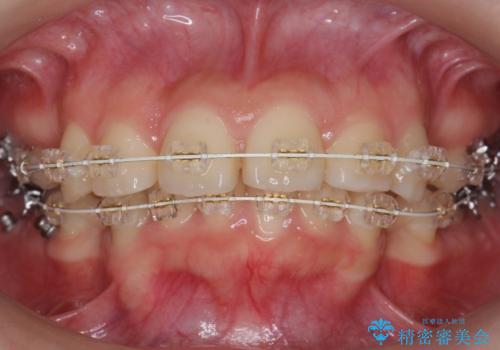

20代女性 出っ歯 口元を引っ込めたい

- 矯正装置

- 審美装置

- 治療計画

- 出っ歯と前歯を気にして来院。

口元を下げたいとのことで、歯を抜いてワイヤー矯正を行いました。

上下左右の小臼歯を抜歯しています。